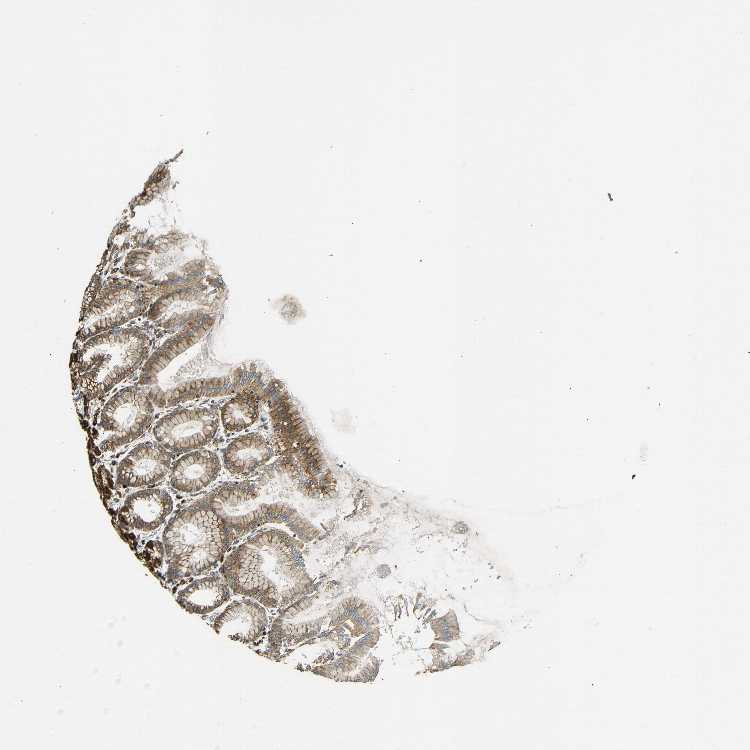

STOMACH 2 - Antibody stainingi

Antibody staining in the annotated cell types in the current human tissue is reported as not detected, low, medium, or high, based on conventional immunohistochemistry profiling in selected tissues. This score is based on the combination of the staining intensity and fraction of stained cells.

Each image is clickable and will lead to virtual microscopy that enables deeper exploration of all samples and also displays staining intensity scores, fraction scores and subcellular localization as well as patient and tissue information for each sample.

Antibody HPA014030

Glandular cells High